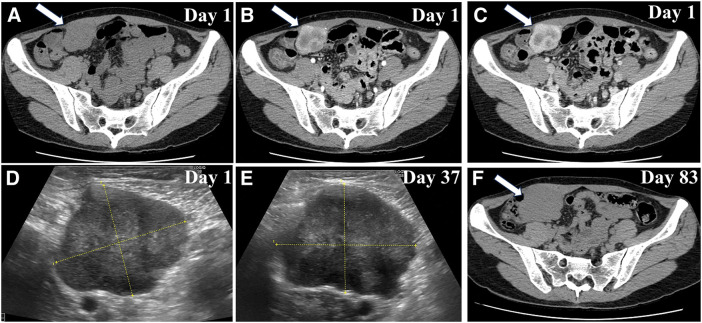

Case presentation: A 38-year-old woman with no significant medical history presented with a rapidly enlarging mass in the right lower abdomen. Computed tomography showed a well-defined tumor on the dorsal side of the right rectus abdominis muscle exhibiting progressive enhancement. Fine-needle biopsy initially suggested the presence of proliferative fasciitis. Owing to rapid tumor growth from 40 to 61 mm within 3 months, laparoscopic surgical resection was performed, including a portion of the posterior sheath and rectus abdominis muscle. Pathological examination confirmed the presence of an IMT and revealed spindle cell proliferation, nuclear atypia, and inflammatory infiltration. Immunohistochemical analysis revealed positivity for smooth muscle actin (SMA) and ALK, partial positivity for desmin, and negativity for cluster of differentiation 34 (CD34) and cytokeratin, compatible with an IMT. WES identified 7 genetic mutations, none of which have been previously reported for IMT in the catalogue of somatic mutations in cancer (COSMIC) database, suggesting novel genetic associations.